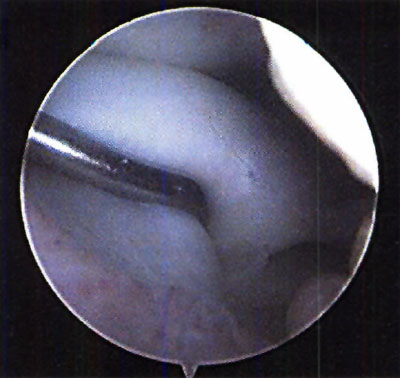

En relación al tratamiento quirúrgico, se realizó debridamiento de la lesión en 6 (26,1%) pacientes, debridamiento y perforaciones en 12 pacientes (52,2%) y en 5 pacientes se efectuó injerto osteocondral (21,7%). (fotos 11 y 12 )

Foto 11: Debridamiento y Perforaciones

Foto 12: cuerpo libre intraarticular